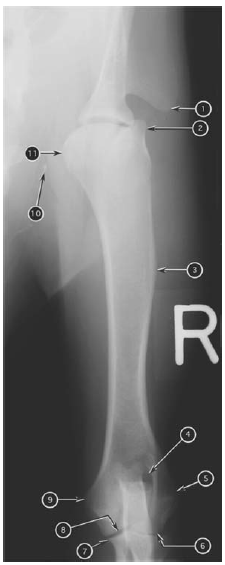

Mediolateral radiograph of canine antebrachium

What number?

- Condyle of humerus

- Lateral epicondyle of humerus

- Medial epicondyle of humerus

- Elbow (cubital) joint

- Tuber olecrani of ulna

- Body of ulna

- Distal metaphysis of ulna

- Distal epiphysis of ulna

- Proximal radioulnar joint

- Head of radius

- Body of radius

- Neck of radius

- Distal metaphysis of radius

- Distal physis of radius

- Distal epiphysis of radius

- Antebrachiocarpal joint

- Accessory carpal bone

- Carpal pad

A

1. Tuber olecrani of ulna

2. Lateral epicondyle of humerus

3. Medial epicondyle of humerus

4. Proximal radioulnar joint

5. Body of ulna

6. Distal metaphysis of ulna

7. Distal epiphysis of ulna

8. Accessory carpal bone

9. Carpal pad

10. Antebrachiocarpal joint

11. Distal epiphysis of radius

12. Distal physis of radius

13. Distal metaphysis of radius

14. Body of radius

15. Neck of radius

16. Head of radius

17. Elbow (cubital) joint

18. Condyle of humerus